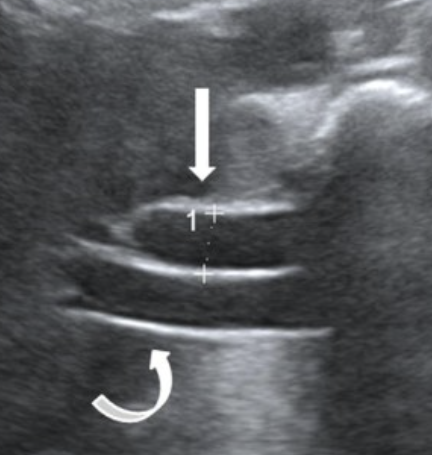

what is the Double Barrel Shotgun Sign?

dilated common bile duct

Portal Vein and Bile Duct near the same size due to dilation of the Bile Duct

See parallel tubular structures in the portal triad with two tubes about the same size.

what is shown?

double barrel shotgun sign